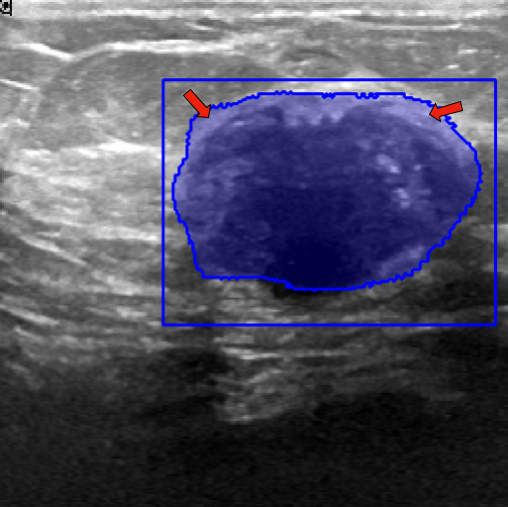

| Fine-Tuning | BUID [70] | 2D Ultrasound | 647 | Breast Cancer Segmentation | ||

| Method | ISIC-2018 (Skin Lesion) | JSRT (Lung X-ray) | KvaSir (Polyp) | Drive (Vessel) | BUID (Breast Cancer) | |

|---|---|---|---|---|---|---|

| Randomly (R50) | 86.16 0.14 | 93.10 0.12 | 62.85 1.32 | 59.82 2.00 | 65.54 0.21 | |

| Pre-trained ImageNet [60] | 86.87 0.47 | 94.52 2.66 | 83.85 1.32 | 65.12 1.55 | 72.64 1.14 | |

| Attention-Unet [77] | 86.81 0.51 | 94.47 2.71 | 82.23 1.41 | 65.02 1.44 | 72.19 1.16 | |

| U-Net ++ [78] | 86.71 0.49 | 94.32 2.81 | 82.23 1.41 | 65.38 0.78 | 73.76 2.83 | |

| 2D Supervised Method | Trans U-Net [76] | 86.60 0.82 | 89.80 0.35 | 67.11 0.24 | 62.63 0.24 | 67.90 0.40 |

| Twin-Barlon [13] | 86.01 0.07 | 94.56 3.09 | 83.00 0.23 | 65.73 1.46 | 74.46 1.19 | |

| Dino [79] | 86.79 0.09 | 94.84 2.79 | 79.84 1.62 | 65.39 0.81 | 76.21 0.57 | |

| SimCLR [15] | 87.28 0.21 | 94.79 2.93 | 82.20 0.51 | 65.22 2.18 | 76.52 0.22 | |

| Moco-v2 [17] | 87.24 0.14 | 94.05 3.52 | 78.24 1.35 | 64.92 2.21 | 75.93 1.96 | |

| Deepcluster-v2 [20] | 86.73 0.42 | 94.79 2.89 | 82.69 0.75 | 64.14 0.92 | 76.33 0.99 | |

| VicRegl [14] | 86.27 0.33 | 94.39 3.25 | 81.93 0.48 | 66.17 0.27 | 75.29 0.64 | |

| 2D-SSL on medical | LVM-Med (R50) | 87.76 0.30 | 95.13 2.64 | 86.76 0.94 | 66.97 0.27 | 78.65 0.72 |

| Clip [3] | 85.98 0.19 | 89.00 1.08 | 72.63 0.37 | 63.01 0.36 | 70.43 0.24 | |

| Flava [5] | 86.42 0.10 | 90.08 0.20 | 69.47 0.05 | 61.09 0.45 | 67.54 1.17 | |

| SAM [6] | 88.17 0.30 | 90.68 0.40 | 70.75 0.60 | 64.04 0.41 | 73.07 0.66 | |

| Foundation Model | LVM-Med (SAM’s ViT) | 88.41 0.28 | 90.74 0.47 | 73.10 0.08 | 65.49 0.12 | 77.20 0.42 |

| SAM (fixed encoder) [9] | 92.42 0.12 | 92.89 5.24 | 89.37 0.57 | 59.74 0.63 | 87.63 0.67 | |

| SAM with Prompt (no-train) [6] | 55.78 0.66 | 61.97 4.48 | 80.77 0.19 | 15.12 0.24 | 78.44 1.01 | |

| Prompt-based Seg. | LVM-Med (SAM’s ViT) | 92.48 0.07 | 93.74 4.06 | 90.09 0.14 | 63.01 0.02 | 89.69 0.61 |

In 3D settings, we segment 2D slices and merge results for a 3D volume. We also benchmarked with 3D self-supervised methods from [86]. Tables (2) and (3) show that our two versions with ResNet-50 and Sam’s ViT hold the best records in each category. For instance, we outperform 2D SSL methods trained on the same dataset, surpassing foundation models such as SAM, Flava, and Clip. In the prompt-based settings, LVM-Med also delivers better performance compared with SAM. Second, LVM-Med achieves the best overall results on seven of eight segmentation tasks, mostly held by LVM-Med with ResNet-50. The improvement gaps vary on each dataset, for e.g., from on Kvasir and BUID compared with 2D supervised methods.